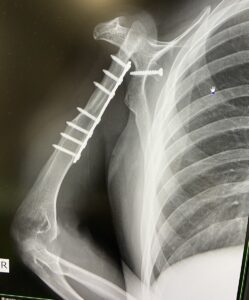

「やはりおかしい…」と感じ、複数の病院へ行きますが、原因が特定できませんでした。最終的には自宅から車で1時間ほど離れた大きな病院でレントゲン撮影を行い、その結果「骨肉腫」と診断されます。

さらに、担当の医師からは「右腕を切断する」といわれたのです。

右肩の骨と筋肉と関節を取り除いたことでハンデを持ったみやびさんは「ハンデを抱えた人が挑戦する姿は、人の心に強く訴える力を持っています。だからこそ、それをマイナスではなく“自分だけの個性”として受け入れたい」と話していました。